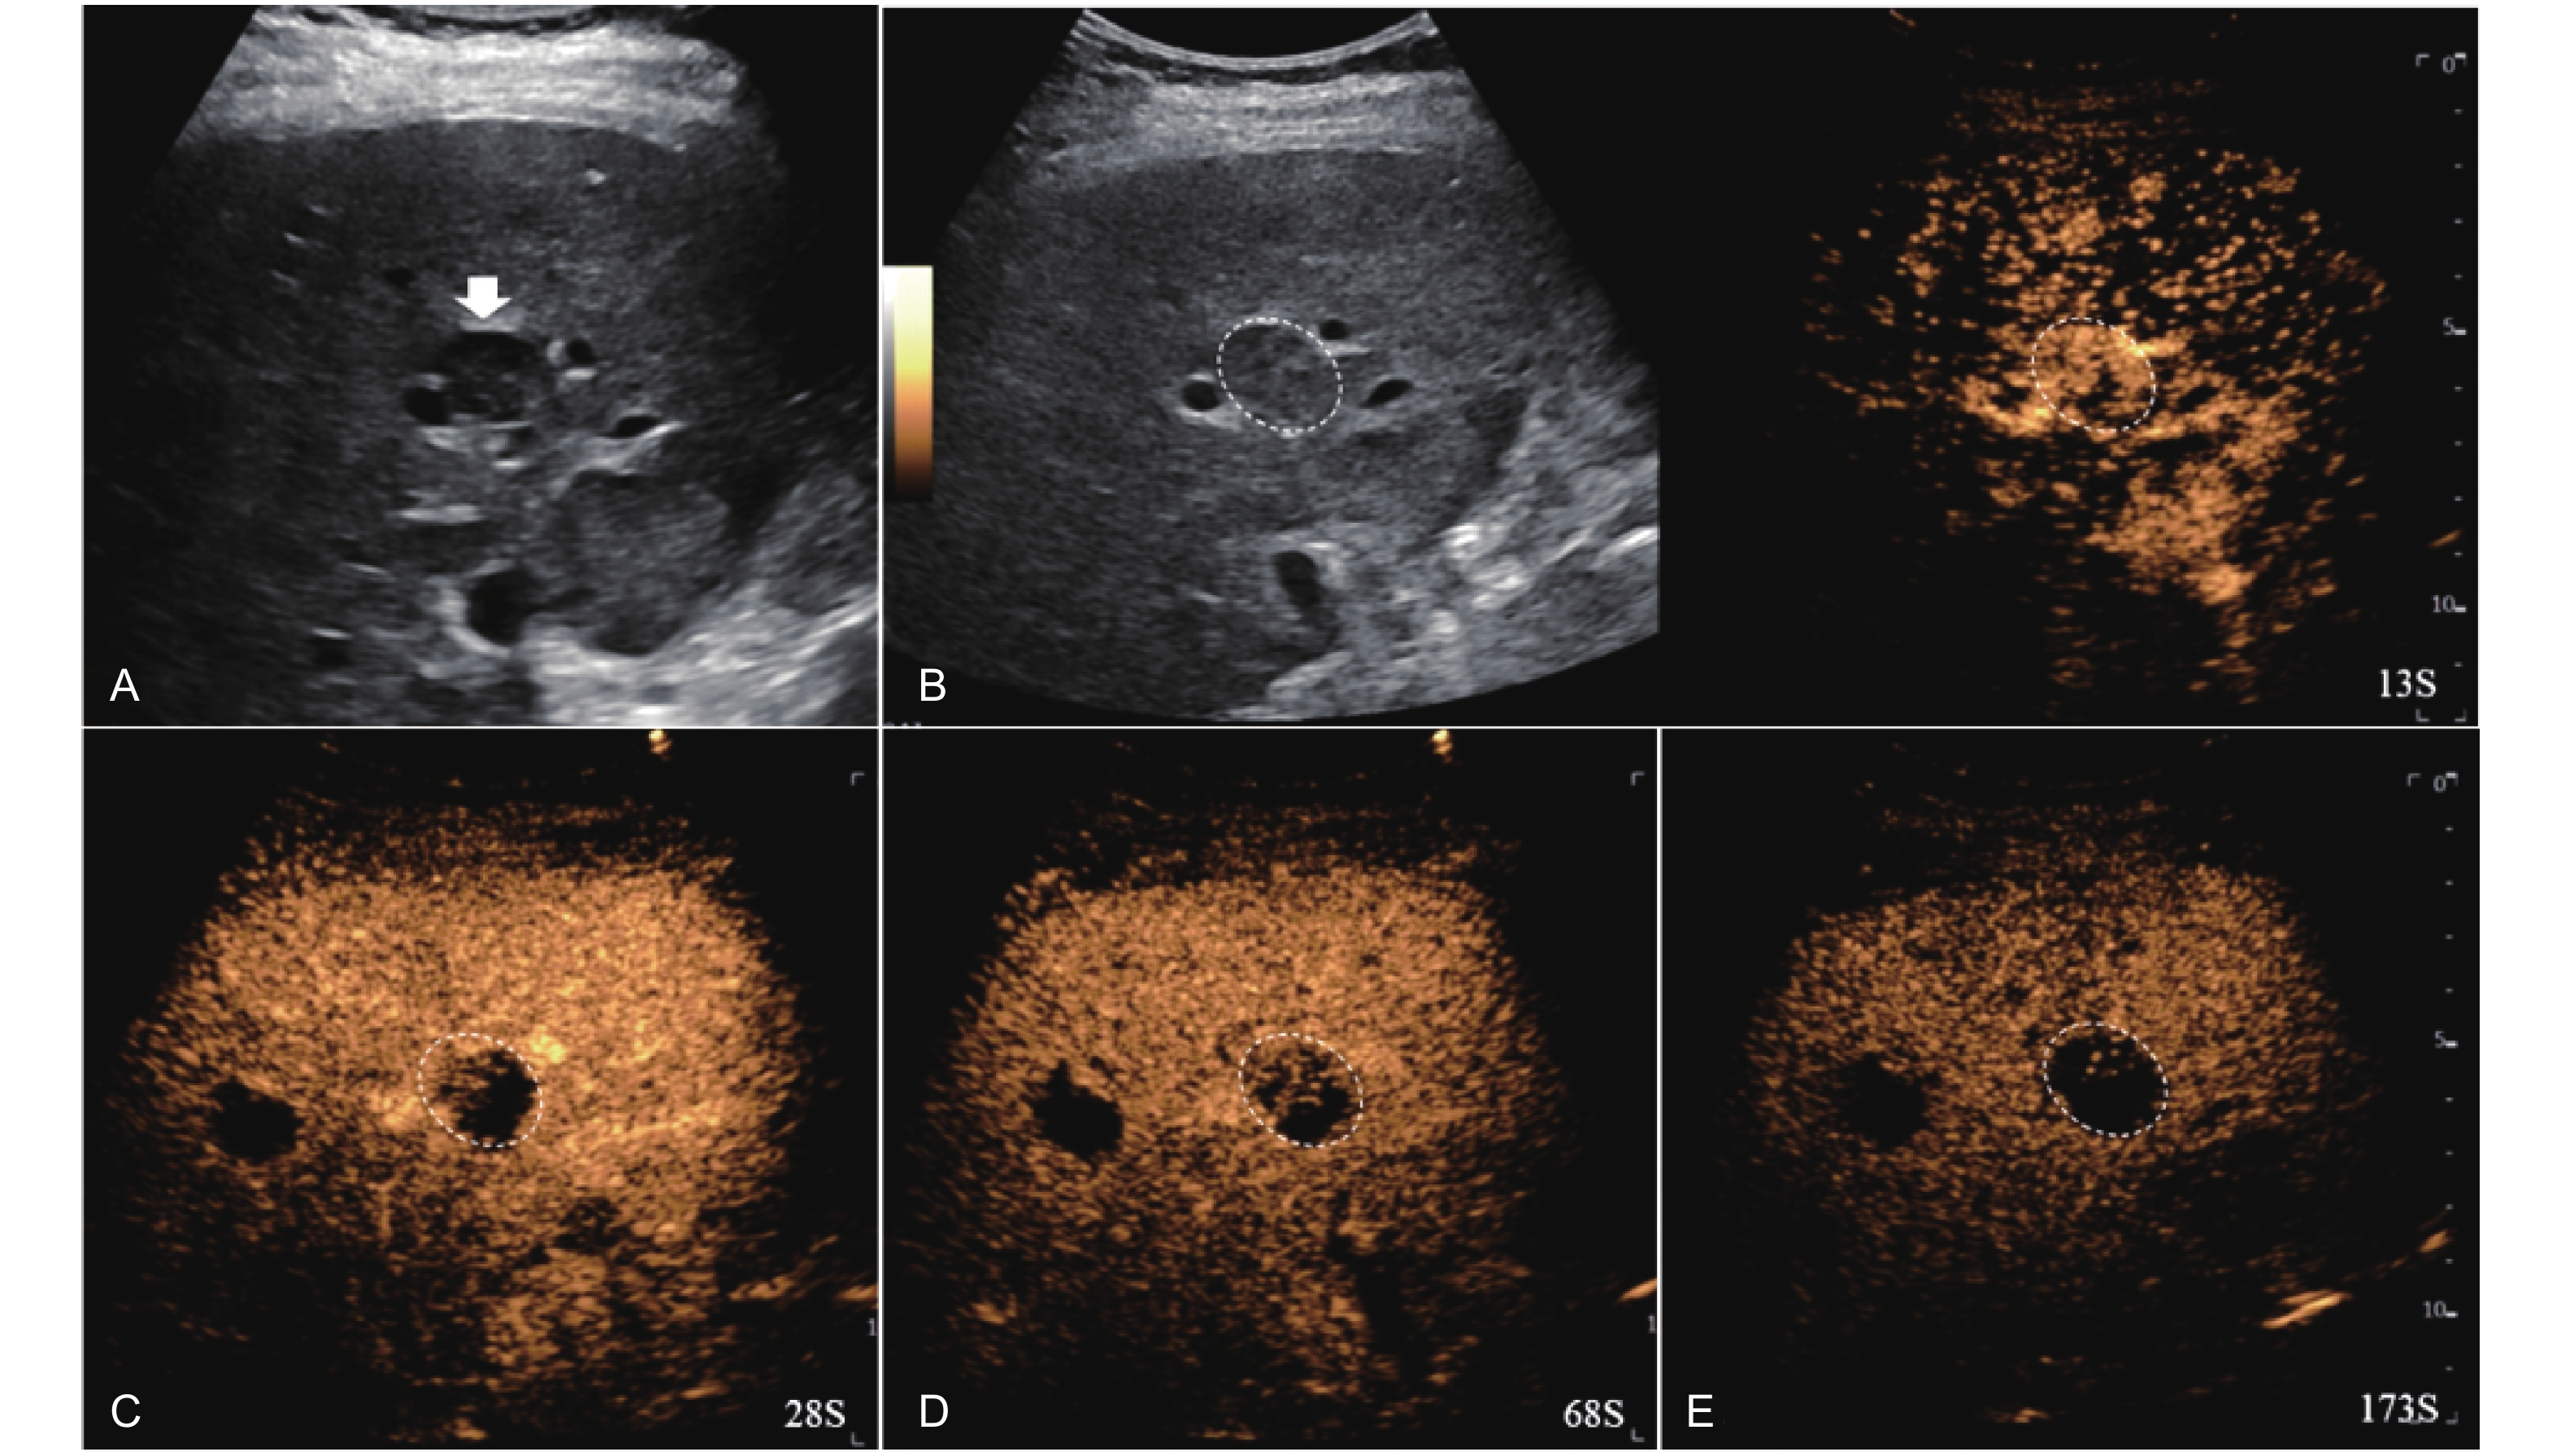

Figure 4

LR-TR Nonviable. Example of a nonviable tumor 14 days after TACE. (A) B-mode image shows two heterogeneous hyperechoic lesions (thick arrow) with irregular shape, measuring 17 mm and 18 mm in segment VI; (B-E) CEUS shows no intralesional enhancement with perilesional enhancement identical to the surrounding liver parenchyma in all phases. Findings are consistent with LR-TR Nonviable."